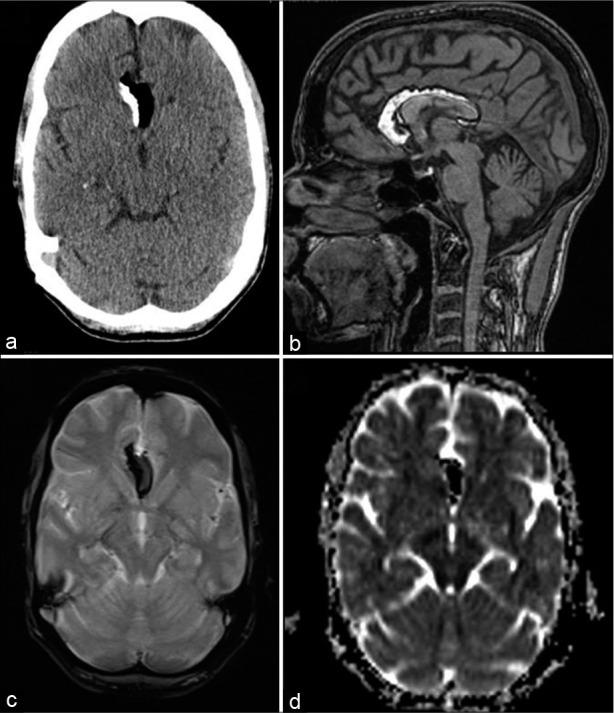

Intracranial lipomas are rare congenital malformations which are present in choroid plexus or subarachnoid locations along the corpus callosum and cisterns. Most of them are identified incidentally during neuroimaging studies done for other indications. Sometimes, they may be associated with other anomalies such as agenesis of corpus callosum and vascular malformations. In magnetic resonance imaging (MRI), they may be associated with chemical shift artifact (CSA) due to their lipid content and can mimic other more serious intracranial lesions. This effect seen in gradient echo MRI sequences can also be used to confirm the presence of these lesions. We report the imaging findings of six patients with intracranial lipomas that showed this chemical shift artifact with a review of the literature.

颅内脂肪瘤是罕见的先天性畸形,存在于脉络丛或沿胼胝体和脑池的蛛网膜下腔位置。它们大多在因其他指征进行的神经影像学检查中偶然发现。有时,它们可能与其他异常有关,如胼胝体发育不全和血管畸形。在磁共振成像(MRI)中,由于其脂质含量,它们可能与化学位移伪影(CSA)相关,并可模仿其他更严重的颅内病变。在梯度回波MRI序列中看到的这种效应也可用于确认这些病变的存在。我们报告了6例显示这种化学位移伪影的颅内脂肪瘤患者的影像学表现,并对文献进行了综述。